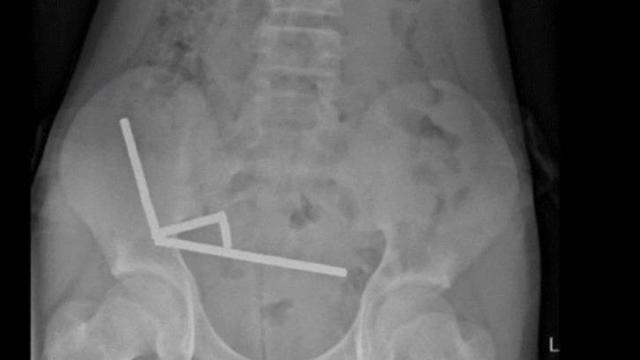

Çocuğunuzun kasığında şişlik varsa dikkat! Acil ameliyet gerekebilir: Kasık bölgesinde fark edilen küçük bir şişlik, çocuklarda ciddi bir cerrahi sorunun habercisi olabilir. Medipol Sağlık Grubu’ndan Çocuk Cerrahisi Uzmanı Op. Dr. Murat Kılıç, “Çocuk fıtığı kendiliğinden iyileşmez, erken dönemde ameliyat edilmesi gerekir. Aksi halde fıtık sıkışarak hayati risk oluşturabilir” dedi.… https://www.eshahaber.com.tr/haber/cocugunuzun-kasiginda-sislik-varsa-dikkat-acil-ameliyet-gerekebilir-268283.html?utm_source=dlvr.it&utm_medium=mastodon EshaHaber.com.tr #çocuksağlığı #kasıkfıtığı #çocukcerrahisi #sağlık #ameliyat